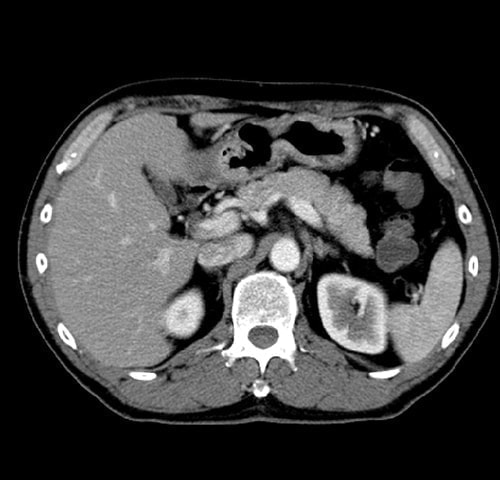

腹部(肝臓・胆のう・ 膵臓・腎臓)病変

※胃の裏でみつかりにくい膵臓がんの発見に有用です

腹部